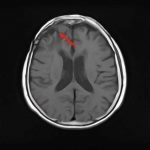

断層撮影